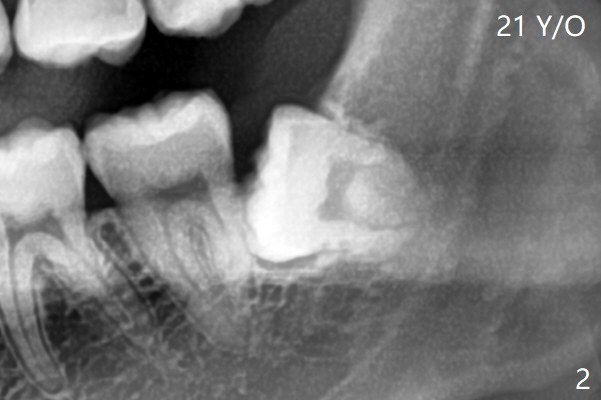

拔除后放置胶原塞(图四)。术后没有神经损伤症状。